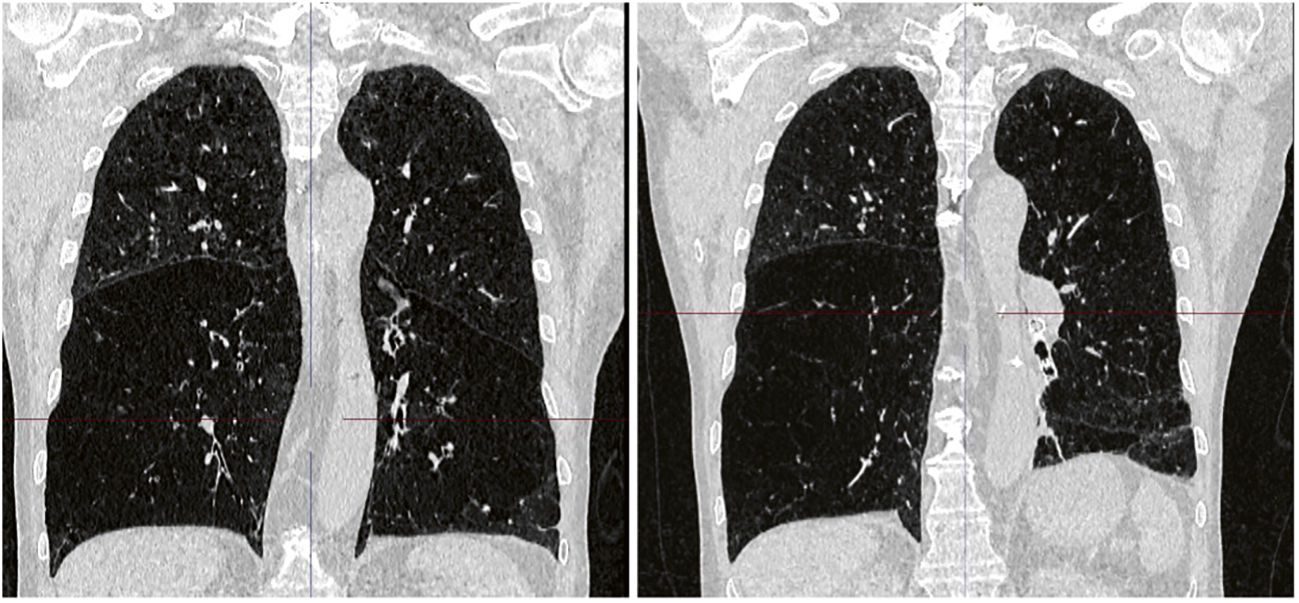

Patienter som lider av svår emfysemsjukdom upplever kronisk andnöd och har nedsatt ansträngningskapacitet och dålig hälsorelaterad livskvalitet. Trots optimal farmakologisk terapi, rökavvänjning och lungrehabilitering förblir majoriteten av patienterna betydligt nedsatta i funktionsnivå. Därför är behandlingen ofta inriktad på symtomlindring och sjukdomskont­roll [1]. Lungvolymreducerande kirurgi kan ge kliniska fördelar hos utvalda patienter med övervägande ovanlobssjukdom och låg funktionsnivå. Dessvärre är denna procedur förknippad med hög perioperativ sjuklighet och dödlighet [2]. Bronkoskopisk lungvolymreduktion är ett alternativ till lungvolymreducerande kirurgi för att minska lungornas hyperinflation. Vid bronkoskopisk lungvolymreduktion placeras enkelriktade ventiler i samtliga segment i en utvald kraftigt hyperinflaterad så kallad mållob (Figur 1). Efter behandlingen töms luften successivt ur loben genom de endobronkiella ventilerna, vilket resulterar i lungvolymreduktion och ofta fullständig atelektas av målloben (Figur 2). I Sverige har två analyser publi­cerats angående behandlingens evidensnivå (health technology assessment, HTA), 2013 och 2018 [3, 4]. Riise et al rapporterade i Läkartidningen 2018 om HTA-analysen som var baserad på 9 randomiserade kontrollerade studier [5-13] och drog slutsatsen att bronkoskopisk lungvolymreduktion med ventiler gav kliniskt betydelsefulla förbättringar i livskvalitet, fysisk prestationsförmåga och lungfunktion hos patienter med emfysem, men att allvarliga komplikationer i direkt anslutning till behandlingen var vanliga, i förs­ta hand pneumotorax [14]. Global Initiative for Chronic Obstructive Lung Disease (GOLD) har på senare år uppgraderat bevisnivån för endobronkiell ventilbehandling till den högs­ta nivån och rekommenderar användning av denna metod för patienter med kroniskt obstruktiv lungsjukdom (KOL) [15].

Figur 1. Schematisk bild av endobronkiella ventiler. Illustration: Pulmonx Inc